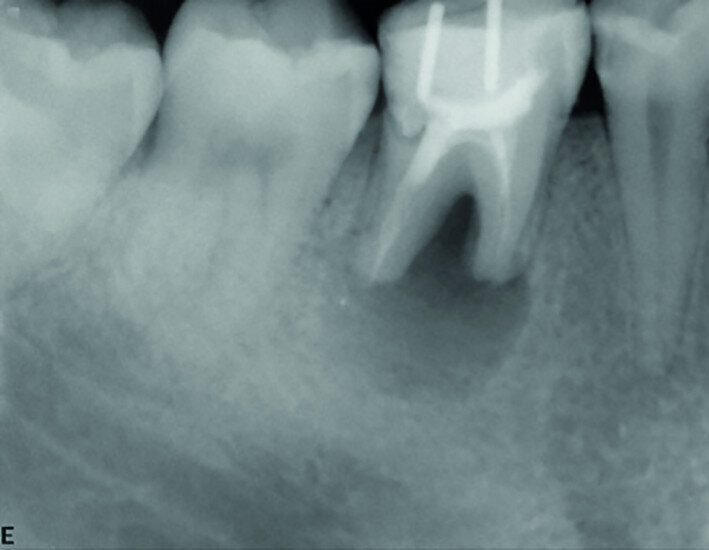

Fig. 9: Post-op periapical radiograph.

After local anaesthesia with 2 per cent mepivacaine with 1:100,000 adrenaline, the right maxillary second molar was atraumatically extracted. Initially with a size 15c surgical blade, the periotomy was realised and then the tooth was extracted after separating the roots to avoid unnecessary trauma to the alveolar bone. Then the donor right maxillary third molar was extracted after periotomy as described and transplanted into the adjacent site. Because of the slight differences in the root anatomy, it was necessary to remove the intraradicular bone septum of the receiving site to al- low tooth positioning, and a odontoplastic of the donor tooth crown was performed to maintain it not in occlusion. An antibiotic (amoxicillin/clavulanic acid, 1 g, by mouth twice a day for five days) was prescribed, along with rinses with 0.2 per cent chlorhexidine. The tooth was keep stable with sutures (Fig. 8). A periapical radiograph was taken (Fig. 9). At the suture removal at two weeks, the tooth showed good stability, and positive adaptation of the soft tissue was observed (Fig. 10). At four weeks, the tooth was stable and the soft tissue looked healthy (Fig. 11). The patient did not show any adverse effects and stated that the tooth was fully functional. Examination of the avulsed second molar showed the extent of the perforation (Figs. 12 & 13).